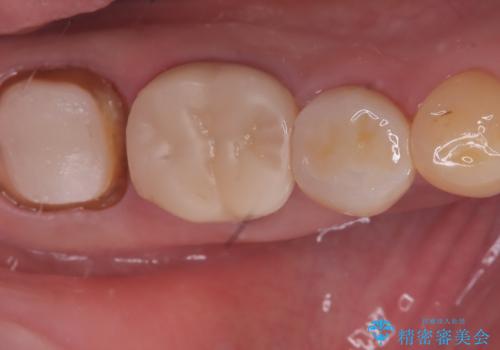

【セラミッククラウン】銀歯を白くしたい

- 主訴:笑った時に下の銀歯が目立つので、白いものに替えたい

失活歯に保険適応のメタルクラウンがセットされていました。

根尖病巣と根管内に破折ファイルを認め、ファイル除去は困難だということをお伝えし、根管治療・土台・クラウンのやり替えとなりました。

根管内破折ファイルの除去が難しいことから、近心根根尖部の洗浄が十分には行えない(病巣が消えない可能性がある)ことを了承いただき治療となりました。